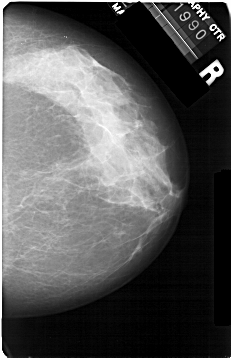

A_1301_1.RIGHT_MLO

RIGHT_CC LINES 5356 PIXELS_PER_LINE 3451 BITS_PER_PIXEL 12 RESOLUTION 43.5 NON_OVERLAY

RIGHT_MLO LINES 5491 PIXELS_PER_LINE 3631 BITS_PER_PIXEL 12 RESOLUTION 43.5 NON_OVERLAY